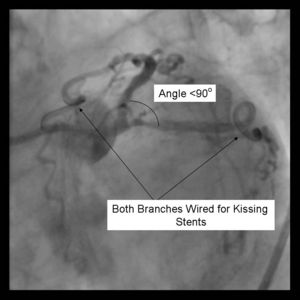

Requires minimum of a 8Fr Guiding system Optimal angle of bifurcation less than 90 degrees.

1) Using a minimum 8Fr guide system, both the parent and side branch are wired. Predilation is recommended to ensure optimal balloon expansion and ease stent delivery. It is important to identify which wire is placed in which branch. We recommend either using 2 separate colored guide wires, keeping a marker on 1 wire, or covering a wire with a sterile towel while not in use.